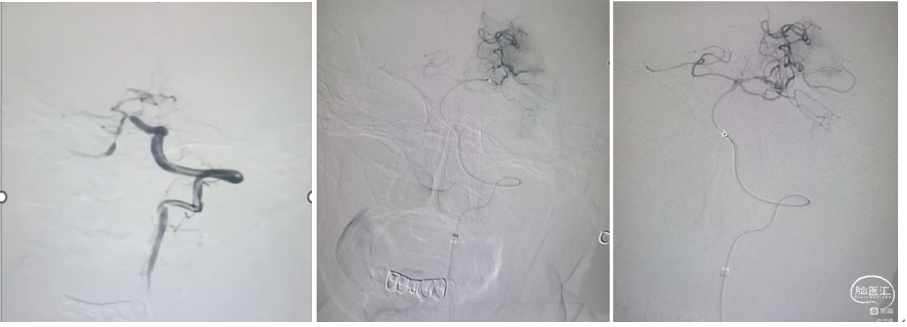

a、右侧VA路图,显示0.014 in的微导丝回头弯穿过闭塞处(白色箭头)将6F抽吸导管(黑色箭头)沿微导管推送至血栓近端。虽然将微导丝穿过血栓可能导致远端栓塞,但当推送抽吸导管需要更强的支撑力时仍需类似操作。

b、右VA路图,将微导丝、微导管移除,抽吸导管嵌入血栓近端,启动负压抽吸。

c.右侧VA造影,取栓术后,单纯抽吸实现成功再通。